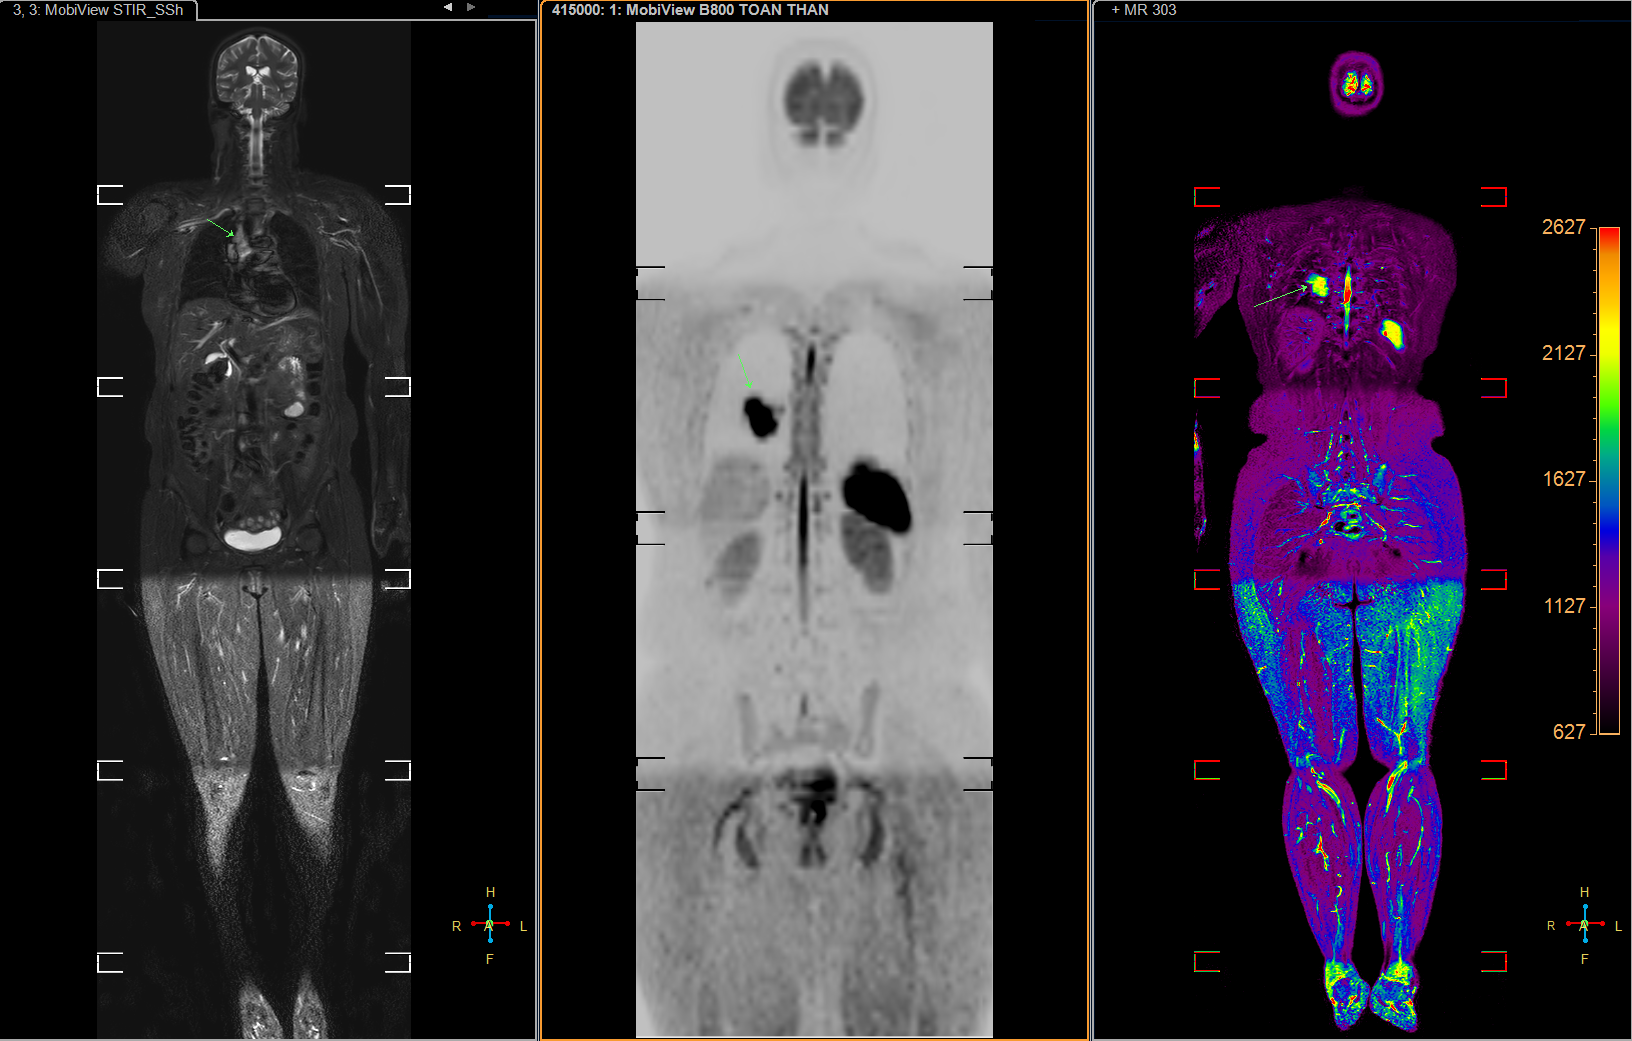

BS. Huỳnh Thị Kim Dung - Giám đốc Bệnh viện đa khoa Vạn Hạnh cho biết, đơn vị áp dụng phương pháp CHT từ toàn thân theo protocol tiêu chuẩn Mỹ, nhằm phát hiện sớm khối ung bướu, phân loại nguy cơ khối u lành và ác. Khâu này giúp quá trình điều trị hiệu quả, đơn giản so với ung thư giai đoạn muộn, góp phần giảm gánh nặng chi phí cho người bệnh lẫn xã hội.

“Vạn Hạnh đã áp dụng mô hình tầm soát ung thư, đột quỵ não trong một lần chụp duy nhất theo tiêu chuẩn Mỹ, giúp người dân tiết kiệm thời gian và chi phí, tạo điều kiện để họ tiếp cận kỹ thuật y học hiện đại dễ dàng, theo chuẩn quốc tế”, BS. Dung nói.

Hệ thống chụp CHT Philips Ambition còn ứng dụng AI giúp tự động hóa quy trình chụp, việc chuẩn bị bệnh nhân chỉ khoảng 1 phút. Với công nghệ Compressed Sense, hệ thống cho phép chụp nhanh hơn 50% với chất lượng hình ảnh đạt độ tương phản cao. Cụ thể, ca chụp thường quy như sọ não, cơ xương khớp mất khoảng 8 phút, chụp tầm soát toàn thân ung bướu và đột quỵ dưới 20 phút.